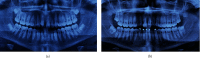

Although ectopic eruption of the maxillary canine has a low prevalence, a late diagnosis can have serious consequences. A careful clinical examination, assisted with radiographic examination, ensures early diagnosis, facilitates planning, and minimizes possible adverse consequences. This study reports a case of ectopic eruption of the permanent maxillary canine, with complete root resorption of the central permanent incisor, the consequences of which caused functional, aesthetic, and psychological harms to the patient. The procedures used included canine ectopic remodeling of the ectopic canine in the central incisor and orthodontic correction, which treated the anomaly and rebuilt the patient's self-esteem.